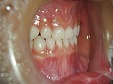

~術前~

オールセラミック修復

~術後~